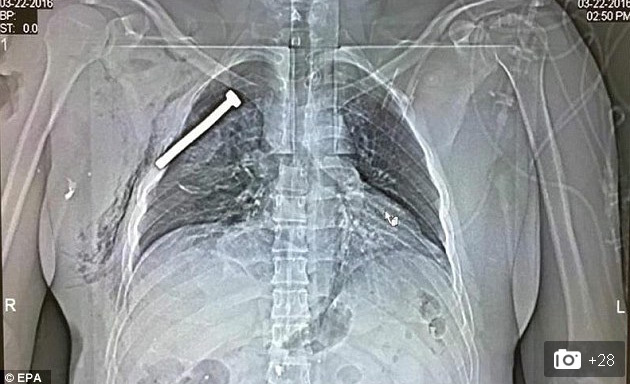

| Bức ảnh X-quang gây sốc cho thấy chiếc đinh nhọn dài 7cm trong lồng ngực nạn nhân vụ đánh bom Brussel |

Đây là bức ảnh chụp X-quang gây sốc vừa được báo chí phương Tây công bố, cho thấy một vật nhọn dài nằm cách trái tim của nạn nhân chỉ vài cm. Các báo cáo của cảnh sát Bỉ cho hay, có ít nhất một quả bom đặt tại sân bay Bỉ có chứa những vật nhọn và đinh sắt kiểu này. Khi bom phát nổ, các đinh nhọn này sẽ bắn ra xung quanh, cắm vào cơ thể nạn nhân và khiến cho mức độ sát thương tăng lên gấp nhiều lần.

Những đinh nhọn này có chiều dài rất khác nhau. Trong ảnh, vật nhọn dài tới hơn 7cm, găm thẳng vào ngực nạn nhân nhưng rất may là người này vẫn sống sót và đang được điều trị tích cực tại bệnh viện Quân đội vùng Neder-over-Heembeek thuộc phía Bắc thủ đô Brussels.